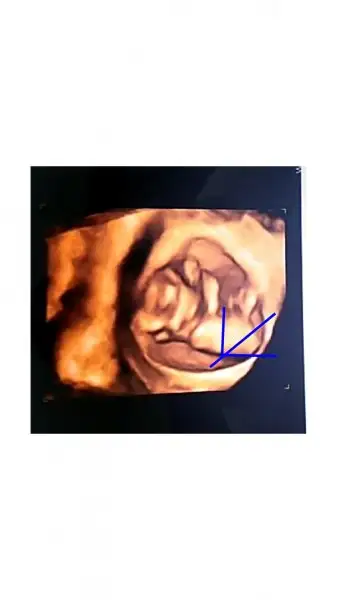

Merhaba arkadaşlar bende buraya bebeğimi atmıstım cinsiyet tahmini için nub cizdigim açı gibiydi.12. Hafta doktor kız dedi.kese konumu kız;çin takvimi kız;etraffımdakiler kız dedi.sadece ben hayır bu bebek erkek ya niye böyle şiddetli erkek hissediyorm inanmıyorum doktora bile dedim.ve bebeğim 16. Haftada pipisini gösterdi biz şok tabi. Kız erkek fark etmez erkek çıktığına kızdan daha cok sevindiğimden değil yanılmadıgıma hisslerimin kuvvetli olduğuna sevindim saglıcakla gelsinler:)

Eklentiler

• Project Capture.webp

Project Capture.webp

5,4 KB · Görüntüleme: 81